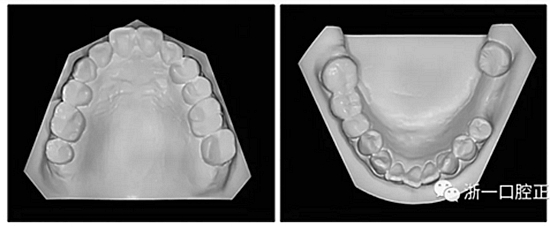

36歲;女性;尋求下頜左后方區(qū)域間隙管理的建議(圖1和圖2),通過(guò)治療獲得了良好的牙頜面效果(圖3和圖4)。她被診斷患有骨性I類(lèi)和代償性牙性II類(lèi)錯(cuò)合畸形,并且上頜左側(cè)尖牙缺失(圖1和2)。大約七年前,由于不可修復(fù)的齲齒,拔除了下頜左側(cè)第一和第二磨牙(圖5)。37相鄰的第三磨牙向近中移動(dòng)并傾斜入間隙,導(dǎo)致無(wú)牙頜間隙減小至約14 mm(圖2和圖5)。臨床和影像學(xué)評(píng)估顯示多發(fā)性齲損和在下頜右側(cè)567處有一不良的固定橋修復(fù)體(圖1和5)。此外,下頜左中切牙缺失,造成下頜中線(xiàn)向左側(cè)偏移約3 mm(圖1和圖2)?;颊咦栽V,她的右上第一前磨牙和左上尖牙在13歲時(shí)由其家庭牙醫(yī)拔除,因?yàn)樗鼈儽蛔枞筋a側(cè)萌出(圖1)。上頜第二磨牙缺失(未知病因),并且相鄰的第三磨牙已經(jīng)轉(zhuǎn)移到第二磨牙間隙中。如補(bǔ)充材料所示,美國(guó)正畸學(xué)差異指數(shù)DI是28分。種植體部位(下頜左側(cè)和右側(cè)第一磨牙)由于復(fù)雜性得到額外4分(補(bǔ)充材料)。

圖2. 治療前牙齒模型